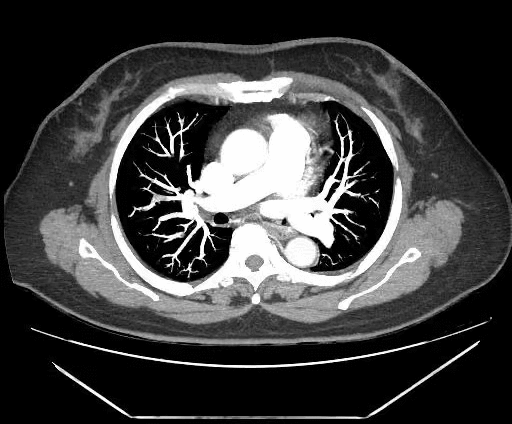

但医生经过仔细观察 CT 影像后还有了新发现,她的双下肢静脉有血栓,肺动脉分支多发肺栓塞。

小腿和肺里都有血栓,这可能是导致黄阿姨呼吸困难的真正原因。